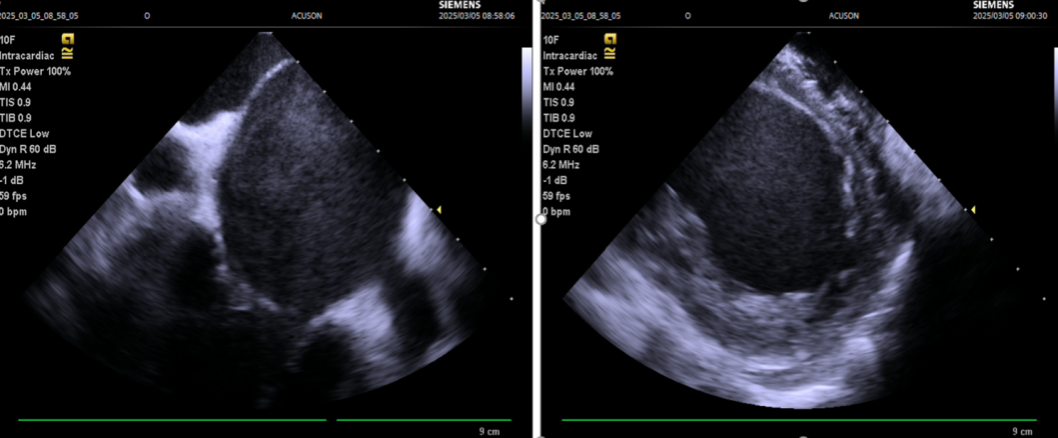

手术在介入导管室的通力配合下进行,姜馨主任、薛建颖主治医师、刘成峰医师密切配合,术中通过右侧股静脉送入心腔内超声(ICE)至右心房,排除左房血栓后成功指导精准房间隔穿刺,沿可调弯鞘管送入锦江心脏脉冲电场消融导管至左房,构建左房三维解剖模型并行基质标测,标测显示左房基质尚可,分别行左侧、右侧肺静脉消融。消融参数:1800v、400ms、400μs,共放电消融148次(消融左上肺静脉时转复为窦性心律),验证双肺静脉均隔离。术后重新标测显示所有肺静脉均已急性阻滞,消融效果理想,肺静脉前庭损伤范围也达到了预期的标准,同时ICE监测未见明显心包积液。手术仅用时30分钟,时间明显缩短,手术过程精准高效。术后患者恢复情况良好并顺利出院。术后1月复查心电图提示窦性心律,心脏超声提示心脏较前明显缩小,收缩功能明显改善,射血分数由25%提升至40%,心功能标记物NT-proBNP 恢复正常,仅54pg/ml。

图1 ICE(心腔内超声)指导下精准房间隔穿刺并实时监测心包积液